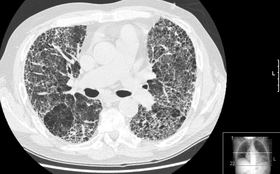

HRCT of lung showing extensive fibrosis possibly from usual interstitial pneumonitis. There is also a large emphysematous bulla. | |

HRCT is used for diagnosis and assessment of Interstitial lung disease, such as pulmonary fibrosis, and other generalized lung diseases such as emphysema, bronchiectasis.

HRCT may be diagnostic for conditions such as emphysema or bronchiectasis. While HRCT may be able to identify pulmonary fibrosis, it may not always be able to further categorize the fibrosis to a specific pathological type (e.g., non-specific intersitial pneumonitis or desquamative interstitial pneumonitis). The major exception is usual interstitial pneumonitis (UIP), which has very characteristic features, and may be confidently diagnosed on HRCT alone.